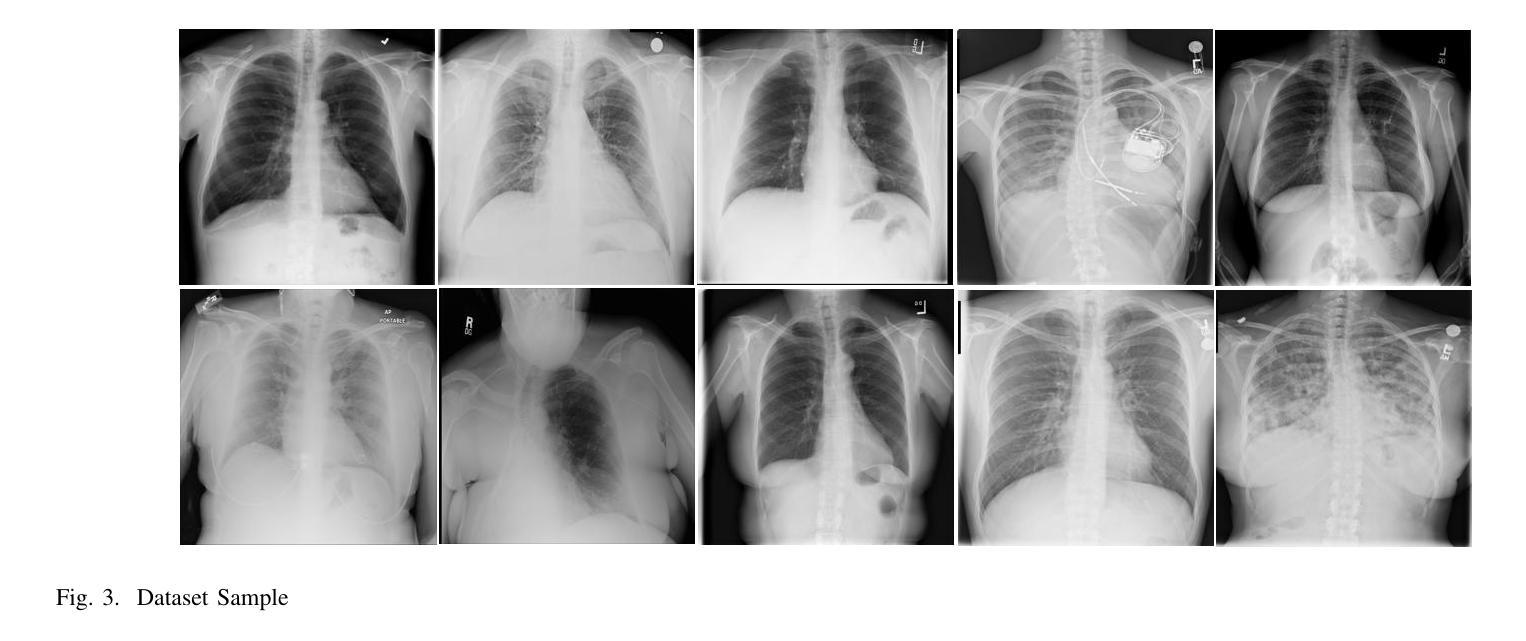

Medical image denoising is essential for improving image quality while minimizing the exposure of sensitive information, particularly when working with large-scale clinical datasets. This study explores distributed deep learning for denoising chest X-ray images from the NIH Chest X-ray14 dataset, using additive Gaussian noise as a lightweight obfuscation technique. We implement and evaluate U-Net and U-Net++ architectures under single-GPU, standard multi-GPU (DataParallel), and optimized multi-GPU training configurations using PyTorch’s DistributedDataParallel (DDP) and Automatic Mixed Precision (AMP). Our results show that U-Net++ consistently delivers superior denoising performance, achieving competitive Peak Signal to Noise Ratio (PSNR) and Structured Similarity Index Method (SSIM) scores, though with less performance in Learned Perceptual Image Patch Similarity (LPIPS) compared to U-Net under low and moderate noise levels. This indicates U-Net++’s enhanced structural fidelity and low perceptual similarity. Meanwhile, our optimized training pipeline reduces training time by over 60% for both models compared to single-GPU training, and outperforms standard DataParallel by over 40%, with only a minor accuracy drop for both models (trading some accuracy for speed). These findings highlight the effectiveness of software-level optimization in distributed learning for medical imaging. This work demonstrates the practical viability of combining architectural design, lightweight obfuscation, and advanced distributed training strategies to accelerate and enhance medical image processing pipelines in real-world clinical and research environments. The full implementation is publicly available at: https://github.com/Suadey/medical-image-denoising-ddp.

医学图像去噪对于提高图像质量并最小化敏感信息的暴露至关重要,特别是在处理大规模临床数据集时。本研究探索了分布式深度学习在NIH Chest X-ray14数据集胸部X射线图像去噪方面的应用,采用高斯噪声作为轻量级模糊技术。我们在单个GPU、标准多GPU(DataParallel)和优化多GPU训练配置下实现了U-Net和U-Net++架构,使用PyTorch的DistributedDataParallel(DDP)和自动混合精度(AMP)。我们的结果表明,U-Net++在去噪性能方面始终表现更优,在峰值信噪比(PSNR)和结构相似性指数方法(SSIM)方面取得了有竞争力的成绩,但在低噪声和中噪声水平下,其在学习的感知图像块相似性(LPIPS)方面的表现略逊于U-Net。这表明U-Net++具有更高的结构保真度和较低的感知相似性。同时,我们的优化训练管道将两个模型相对于单个GPU训练的时间缩短了超过60%,并且相较于标准的DataParallel提高了超过40%,同时两个模型的精度略有下降(以牺牲一些准确性换取速度)。这些发现突显了软件级优化在医学成像分布式学习中的有效性。这项工作证明了结合架构设计、轻量级模糊技术和先进的分布式训练策略,可以加速和改进真实临床和研究环境中的医学图像处理流程的实际可行性。完整的实现可公开访问:https://github.com/Suadey/medical-image-denoising-ddp。

本研究探讨了基于分布式深度学习的医学图像去噪技术,特别是针对胸部X射线图像的应用。研究采用了NIH Chest X-ray14数据集,使用添加高斯噪声作为轻量级混淆技术。研究实现了U-Net和U-Net++架构,并在单GPU、标准多GPU和优化多GPU训练配置下进行了评估。结果显示,U-Net++在去噪性能上表现更优秀,在峰值信噪比(PSNR)和结构相似性指数方法(SSIM)方面表现出竞争力,但在低噪声和中噪声水平下感知图像块相似性(LPIPS)方面的表现略逊于U-Net。这表明U-Net++具有更高的结构保真度和较低的感知相似性。同时,优化训练管道将两个模型的训练时间减少了60%以上,与单GPU训练相比提高了性能,并优于标准DataParallel训练,但以轻微的性能下降为代价。该研究展示了结合架构设计、轻量级混淆和高级分布式训练策略在实际临床和研究环境中加速和改进医学图像处理流程的实用性。